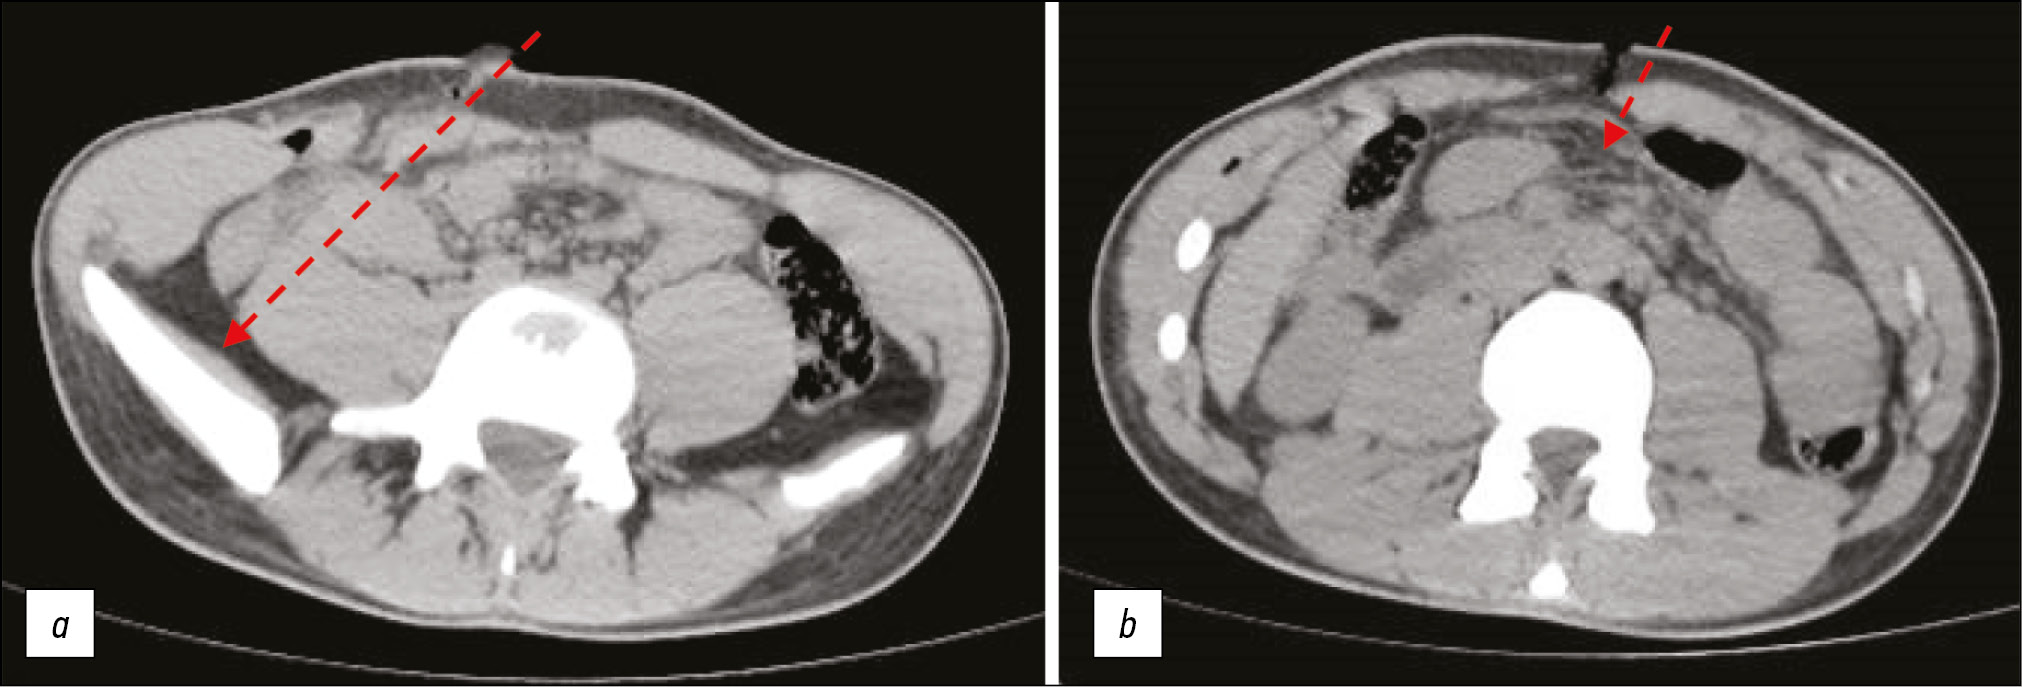

- рана на груди слева по окологрудинной линии в проекции IV ребра (проникает в плевральную полость): судя по ателектазу левого лёгкого, раневой канал направлен спереди назад, снизу вверх и слева направо (рис. 2, а).

Рис. 2. Данные компьютерной томографии потерпевшего М.: а ― ателектаз левого лёгкого по ходу раневого канала (стрелка); b ― разметка смещения раневого канала на послойных снимках. / Fig. 2. Computed tomography data of the victim M.: а ― atelectasis of the left lung along the course of the wound canal; b ― marking of the displacement of the wound canal on layered images.

КТ позволила чётко установить направление раневых каналов с учётом смещения повреждения тканей на послойных снимках. На основании этих данных была выполнена разметка отклонения канала в сантиметрах (рис. 2, b).